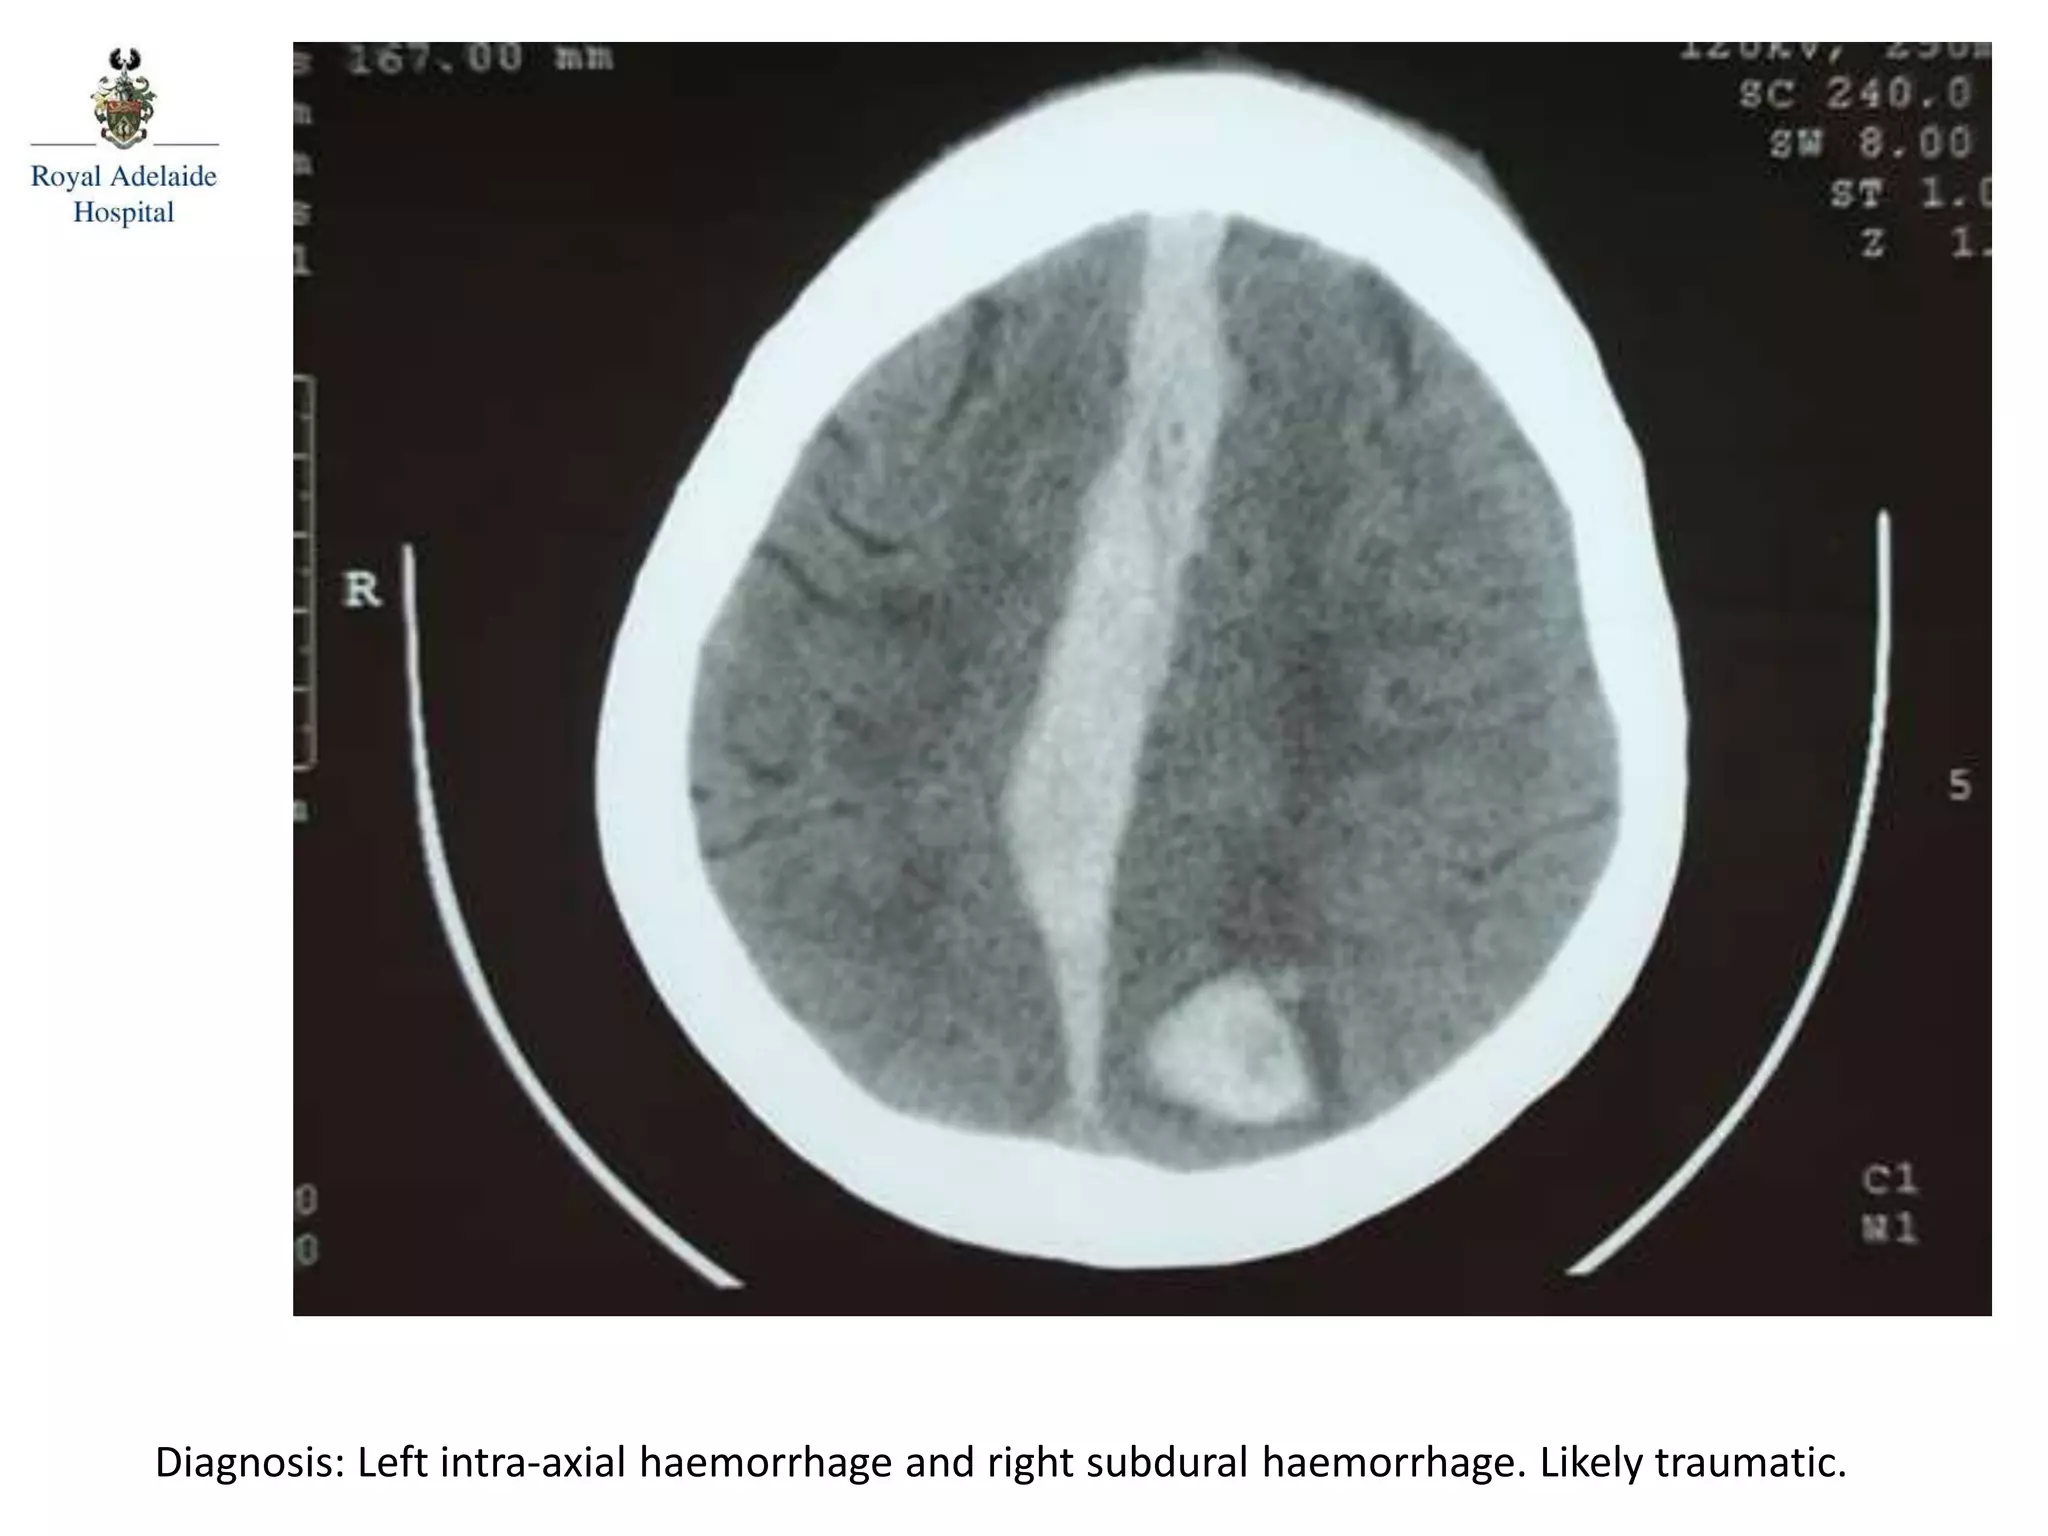

The document outlines multiple diagnoses from head CT cases, including small left basal ganglia bleed likely due to hypertension, various types of subdural and subarachnoid hemorrhages, and evidence of hydrocephalus. It details traumatic origins of some hemorrhages and notes obstructing masses and atrophic changes. Overall, there are significant findings indicating complications related to cerebral hemorrhages and ventricular enlargement.